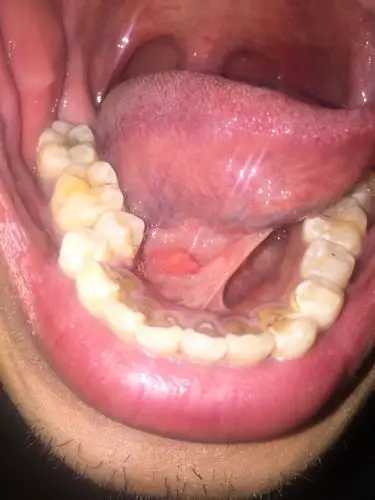

口腔里,舌头下面,但不是舌头上长了个肉芽.